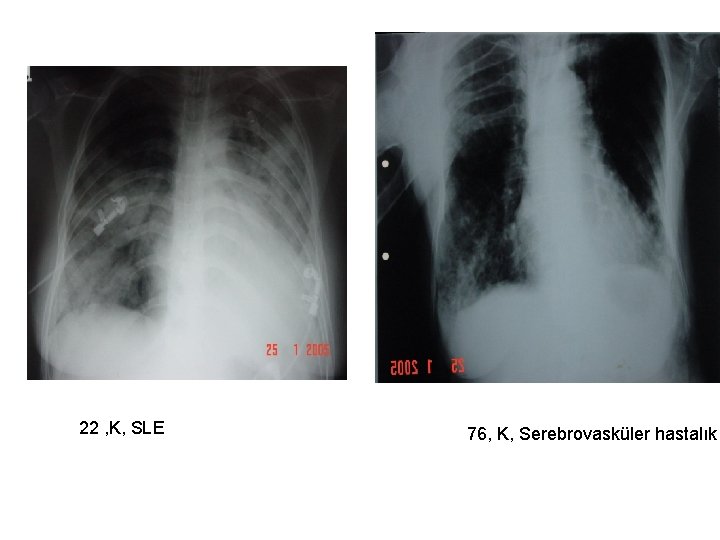

22 , K, SLE 76, K, Serebrovasküler hastalık